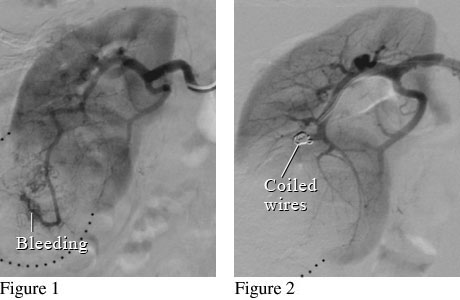

Angiogram of a Renal Mass